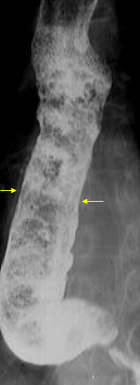

Varice esofagiene